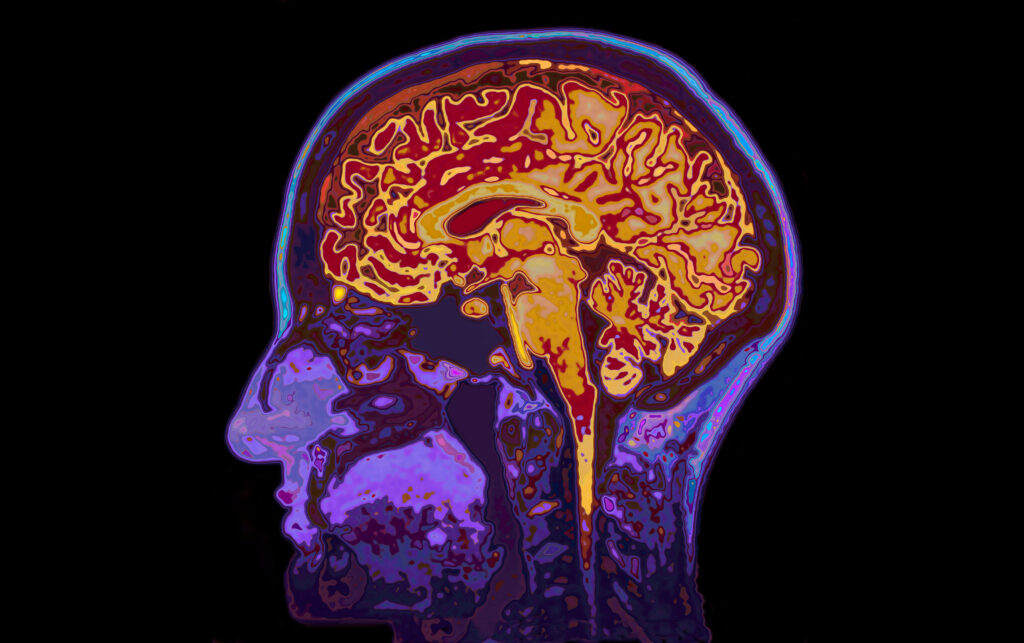

Lembke untersucht eine zentrale Triebkraft unseres Daseins: Das dopamingesteuerte Belohnungssystem im Gehirn. Dopamin, ein wichtiger Botenstoff im Körper, beeinflusst maßgeblich unser Lust- und Glücksempfinden sowie unsere Motivation. Das Gehirn schüttet Dopamin aus, um uns in einen aufgeregt-angespannten Zustand zu versetzen, damit wir motiviert auf eine erwartete Belohnung hinarbeiten. Das eigentliche Glücksgefühl beim Erreichen der Belohnung wird jedoch durch andere Botenstoffe wie Serotonin vermittelt. Lembke beschreibt diesen Mechanismus als „Mehr Wollen als Mögen”: Der Drang nach einer Belohnung ist oft stärker als das tatsächliche Vergnügen daran – ein Effekt, der zur Entstehung von Süchten beitragen kann. Die Redewendung „Vorfreude ist die schönste Freude!” veranschaulicht treffend die Funktionsweise unseres Belohnungssystems.